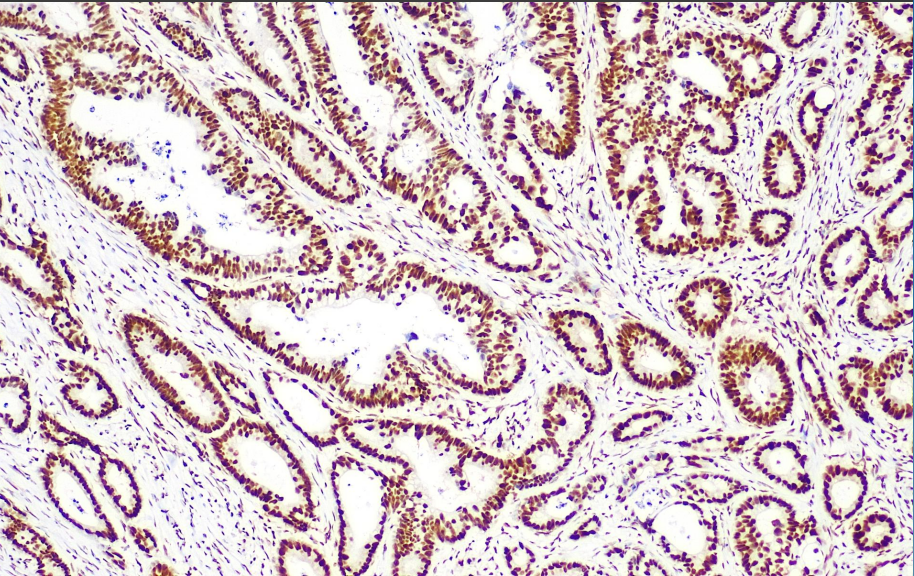

Cellular localization: nucleus

Positive control: Colorectal cancer

The DNA Mismatch Repair System consists of enzymes that specifically repair DNA base mismatches to ensure high fidelity of DNA genetic material.The MLH1 gene is located on chromosome 3, and the 87kD protein product it encodes under normal conditions helps to repair errors arising from DNA replication. It is mainly used in tumor research.

The MLH1 antibody reagent can specifically bind to the MLH1 molecular antigen. The immunohistochemical kit containing the MLH1 antibody reagent is suitable for the precise diagnosis of Lynch syndrome (hereditary non-polyposis colorectal cancer, HNPCC) and sporadic microsatellite instability (MSI-H) tumors.